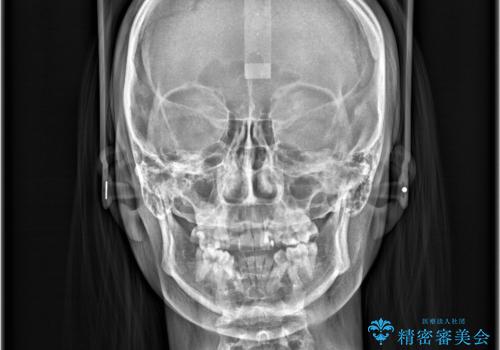

- 治療計画

- 「歯のでこぼこを治したい」を主訴に来院された患者様です。 上下ともに、歯のでこぼこが強く、上下左右4の抜歯をし、ワイヤー矯正で治療を行いました。

かなり綺麗に並ぶ事ができ大変満足していただけました。

叢生量がかなり多かったのですが、歯肉退縮も失活歯も無くとても綺麗な歯並びになりました。